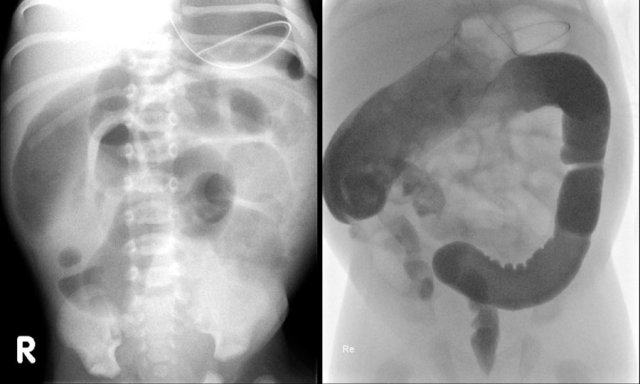

Hirschsprung disease

In Hirschsprung disease ganglion cells are absent in the distal part of the colon.

Because the intestinal ganglion cells migrate in a craniocaudal direction, the area of aganglionosis always involves the rectum.

More extensive disease extends orally in a contiguous fashion.

The involved bowel has a small diameter and the bowel proximal to the affected segment is dilated.

In Hirschsprung disease the ratio between the denervated and the non-affected bowel is <1.

It is important to describe the length of the affected segment.

Most cases are short-segment and total aganglionosis is rare.

In case of total aganglionosis the diagnosis is difficult, because the entire colon has a small caliber and resembles a microcolon.

Start the enema in the lateral position to evaluate the rectum.

Save cine images from the first contrast injection, as with progressive filling signs can become obscured by too much bowel distention.

Normally the rectum should be wider than the sigmoid.

The image shows an abnormal recto-sigmoid index <1.

Here another case of Hirschsprung disease.

The definitive diagnosis of Hirschsprung disease is confirmed with biopsy.